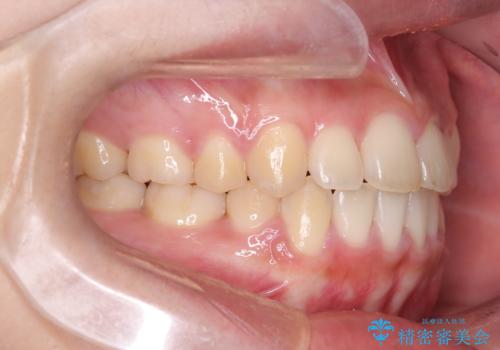

- 八重歯と口元が出ていることを主訴に来院されました。

レントゲンの検査において、前歯も外側に傾いてる結果であったため、上下左右の小臼歯を抜歯して配列を行いました。

歯の動きも良く短期間で治療を終えられたため患者さんにも大変満足していただきました。